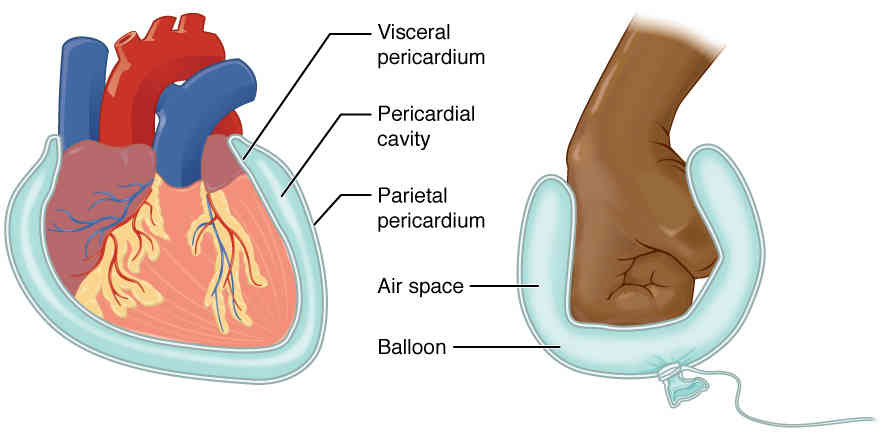

This page is under construction. For now, it is just a resource of the images found in the OpenStax Anatomy and Physiology Handbook. It wil slowly change into a revision tool. Each slide has a number. Use this to refer to the slide. When completed, it will have an unlabelled section, with labelled slides in parallel. On the unlabelled slides, write your answer and use the labelled slide to assess yourself. Keep track by also noting the number on each slide. Improvement at each attempt is important, more so than full marks on a first attempt.